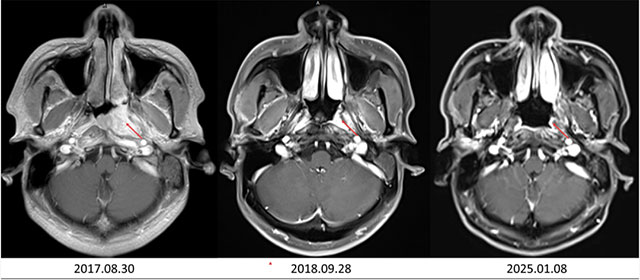

经过系统治疗后,李大哥的左耳胀闷、听力下降等症状逐渐缓解,肿瘤也得到了有效控制。治疗结束后,李大哥严格遵循曾瑞的嘱咐,定期复查、规律作息、合理饮食,坚持中医调理。

如今,8年多时间过去,李大哥已完全回归正常生活,不仅能照顾家人,还能正常工作。

近日,他再次来到医院复查,检查结果显示病情无复发转移,达到了“临床治愈”的标准。